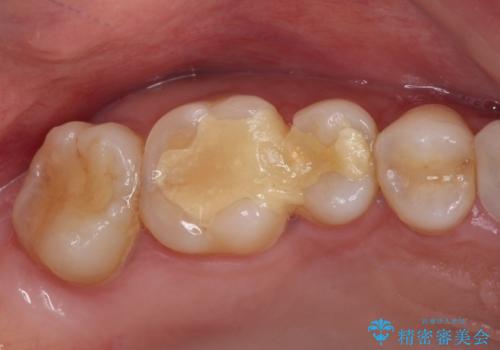

上顎臼歯は、おそらく銀歯を外して仮詰めされていたため、再度形を整え、セラミックインレーにて修復治療を行うこととしました。